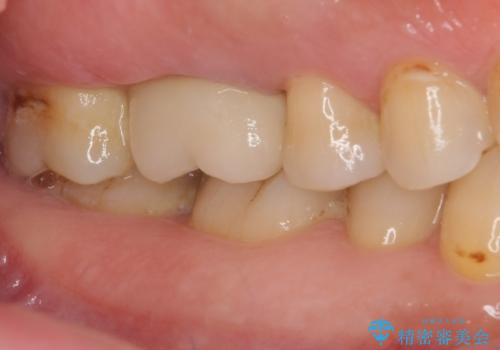

歯周外科処置を併用した奥歯の補綴治療

- クラウンが装着された奥歯から、歯磨きの度に出血するとのことで来院された患者様です。

虫歯が歯肉の奥深くにまで及んでおり、歯肉が腫れやすい状態となっていたため、歯肉の切除並びに歯槽骨の形態修正を行い、虫歯が歯肉の外に出てくるようにした上で、オールセラミックにて補綴することとしました。

歯間ブラシを通す度に出血をするのは、ご自身の磨き方が悪いからと思っていらっしゃいましたが、治療後は全く出血することがなくなり、患者様には大変満足していただきました。